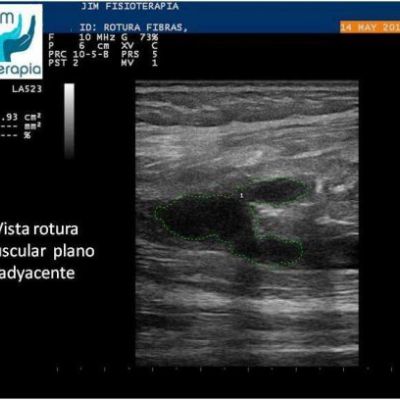

Varón de 47 años, sufre una rotura muscular en el bíceps femoral de la pierna derecha al realizar una brusca contracción excéntrica asociada a movimiento de torsión, al evitar la caída de su motocicleta. Acude a las 72 hrs a nuestra clínica presentando dolor a la palpación, contracción muscular y en la marcha. En la exploración ecográfica se observa una rotura de bordes irregulares.

Se procede a la aplicación de EPI® con el fin de “vaporizar” el derrame producido y favorecer el proceso de regeneración y cicatrización muscular sin fibrosis. En las imágenes se puede apreciar el cambio en el tejido desde la primera sesión, fueron necesarias cuatro sesiones de EPI® hasta lograr la recuperación completa, a partir de la segunda sesión el paciente refirió una desaparición del dolor en la marcha y las actividades cotidianas, complementando su tratamiento con la aplicación de Radiofrecuencia.